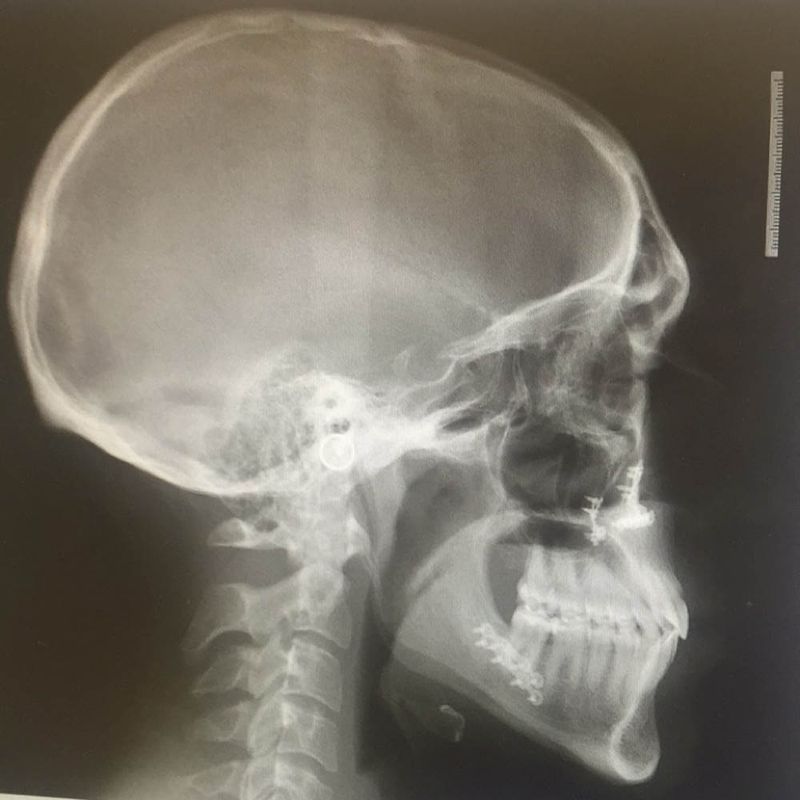

Dr. Dyer underwent orthognathic surgery himself to correct his Class III malocclusion (also known as an underbite). Having personally gone through the process, he can truly empathize with patients and offer valuable insights from a patient’s perspective, making your journey easier.

Before

After